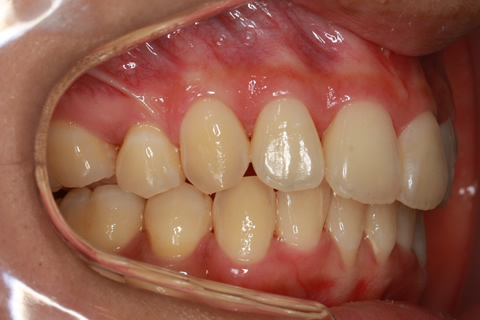

治療中

治療後